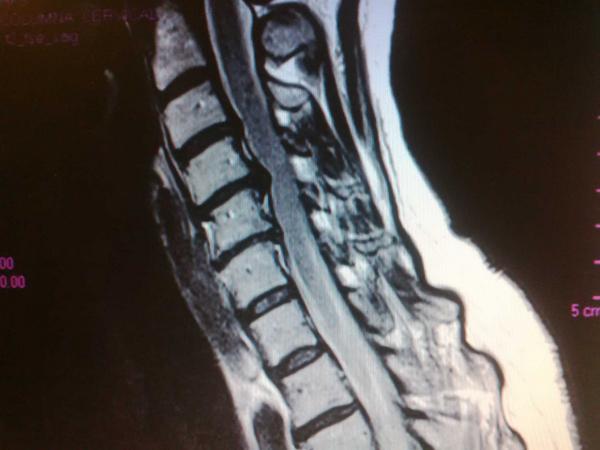

Radiculopatia Cervical En Un Paciente Con Ocho Vertebras Cervicales Presentacion De Un Caso Leyva Velazquez Multimed